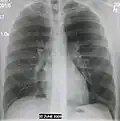

AP CXR showing left lower lobe pneumonia associated with a small left sided pleural effusion -

AP CXR showing right lower lobe pneumonia -

AP CXR showing pneumonia of the lingula of the left lung -

Left upper lobe pneumonia with a small pleural effusion.